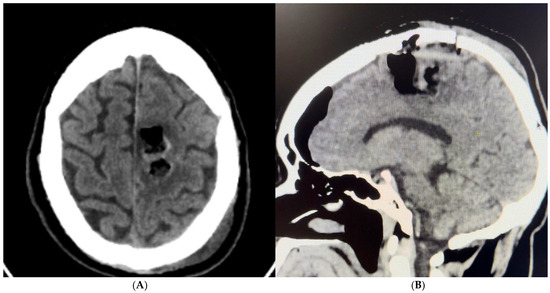

- Case 1: The AR-assisted retrosigmoid approach facilitated an 80% subtotal resection of a complex infratentorial meningioma, resulting in significant symptomatic relief and minimal postoperative complications. This underscores the potential of AR to enhance surgical outcomes in challenging anatomical regions (on the sigmoid and transverse sinuses). (Figure 1 and Figure 2). The patient’s rapid recovery and favorable outcome further emphasize the clinical advantages of AR-guided surgery.